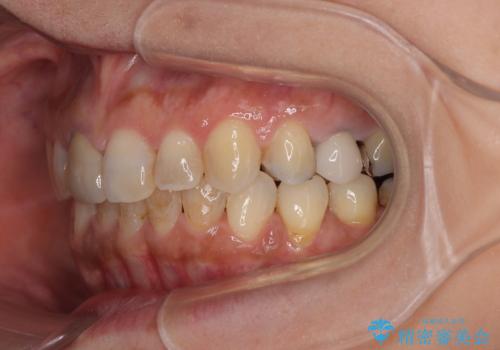

痛みがなくなり歯列が整ったことで、残っている銀歯も気になり始めているようです。

マウスピース生活に疲れてしまったとのことで、暫くお休みをしてから銀歯の治療を再開していく予定です。